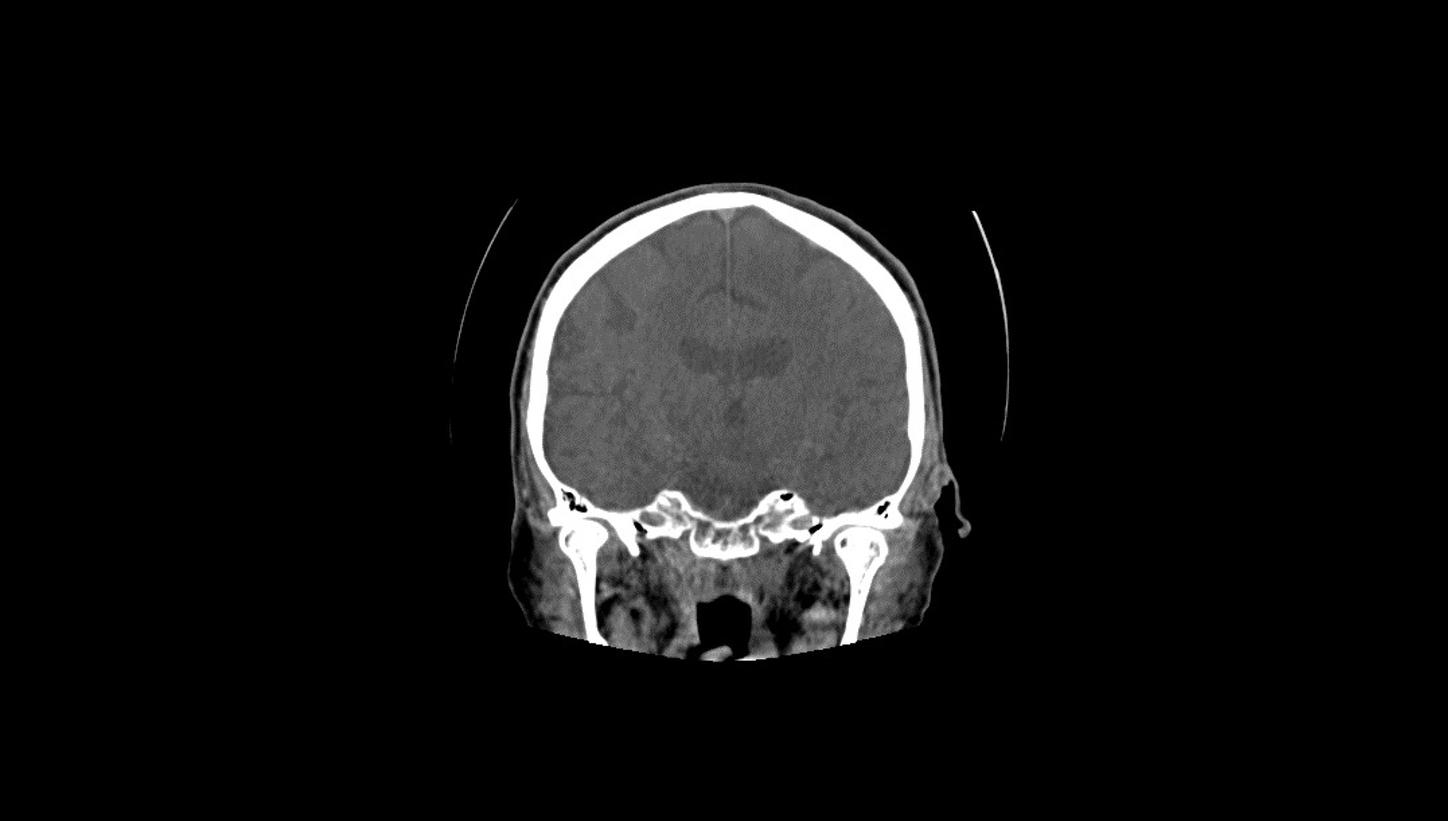

Native head scan

Assist with or support differential diagnosis of acute stroke with excellent gray-white matter differentiation and contrast enhancement